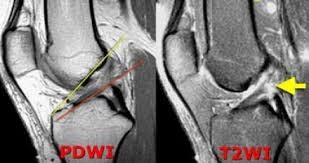

Για να γίνει σωστή διάγνωση μία ρήξης χιαστού συνδέσμου πρέπει να συμφωνούν η κλινική αξιολόγηση του πάσχοντος από τον ορθοπεδικό με την μαγνητική τομογραφία που θα γίνει (12-15 ημέρες μετά τον τραυματισμό για να έχει υποχωρήσει το οίδημα). Δηλαδή τα τεστ αξιολόγησης σταθερότητας του γόνατος να είναι σύμφωνα με εικόνα ρήξης από το απεικονιστικό μέσο. Τα τεστ που υπάρχουν για την αξιολόγηση μίας ρήξης υποδεικνύουν κάκωση αν δεν υπάρχει σταθερότητα στο γόνατο και θεωρούνται θετικά αν και η σύγκριση με το υγιές μας οδηγήσει σε αυτό το συμπέρασμα.

Μερικές εικόνες από μαγνητικές με ρήξη του προσθίου χιαστού συνδέσμου